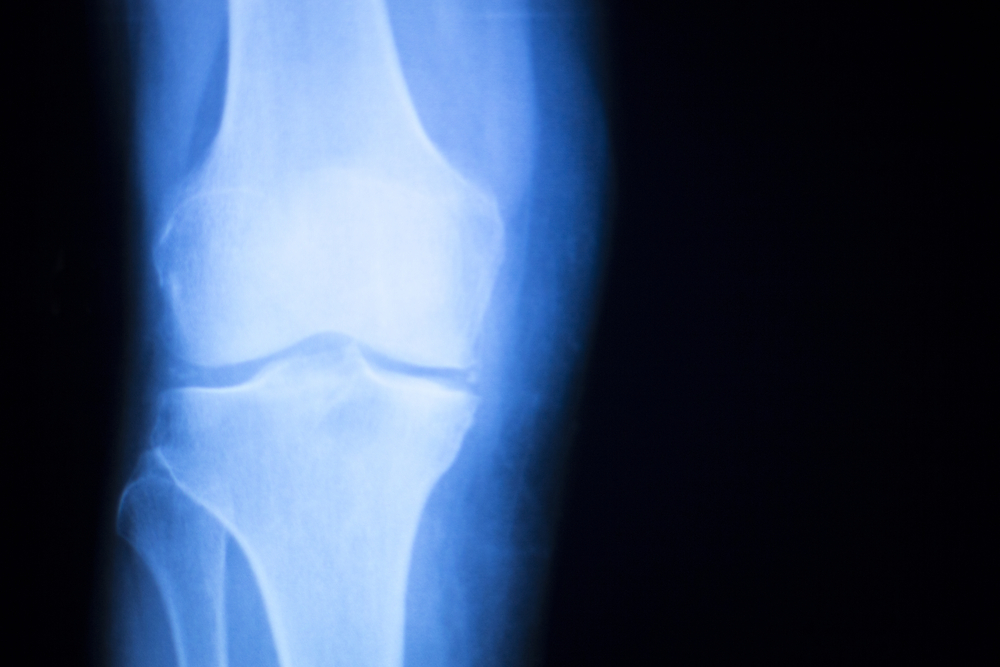

Does Anything Restore Knee Cartilage?

Restoring knee cartilage, particularly in cases of significant damage or degeneration, is challenging, as cartilage has limited ability to heal on its own due to its avascular nature (lack of blood vessels).